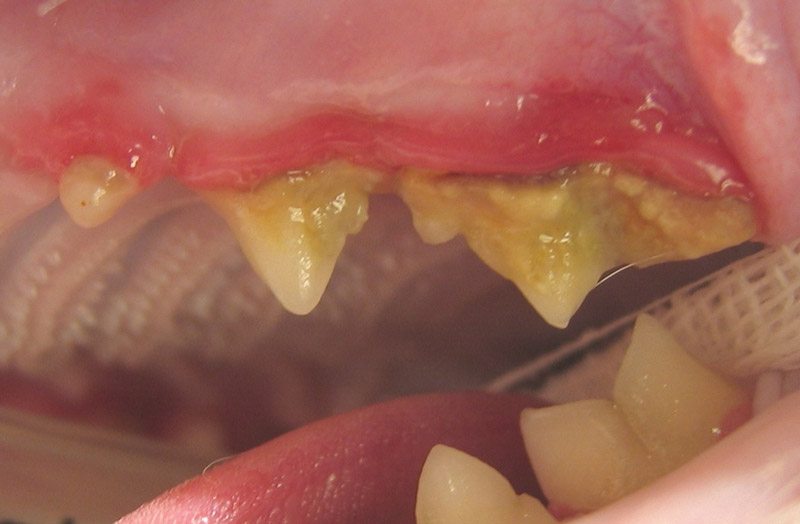

Istraživanja pokazuju da se „parodontalna bolest“ – zajednički naziv za nekoliko inflamatornih stanja u ustima – javlja kod 70% mačaka u vreme kada napune tri godine*. Možda niste ni svesni da nešto nije u redu jer je simptome teško otkriti, ali, osim što izazivaju bolno oštećenje u ustima mačke, ako se ne leče, uključene bakterije mogu da utiču na druge delove njihovog tela. To znači da briga o ustima vaše mačke treba da bude važan deo vašeg preventivnog zdravstvenog režima. Na sreću, postoji nekoliko jednostavnih koraka koje možete preduzeti da biste pomogli u održavanju oralnog zdravlja vaše mačke i na taj način ih spasili od potencijalno velike nelagodnosti i bola. Da biste saznali više, posavetujte se sa vašim veterinarom.